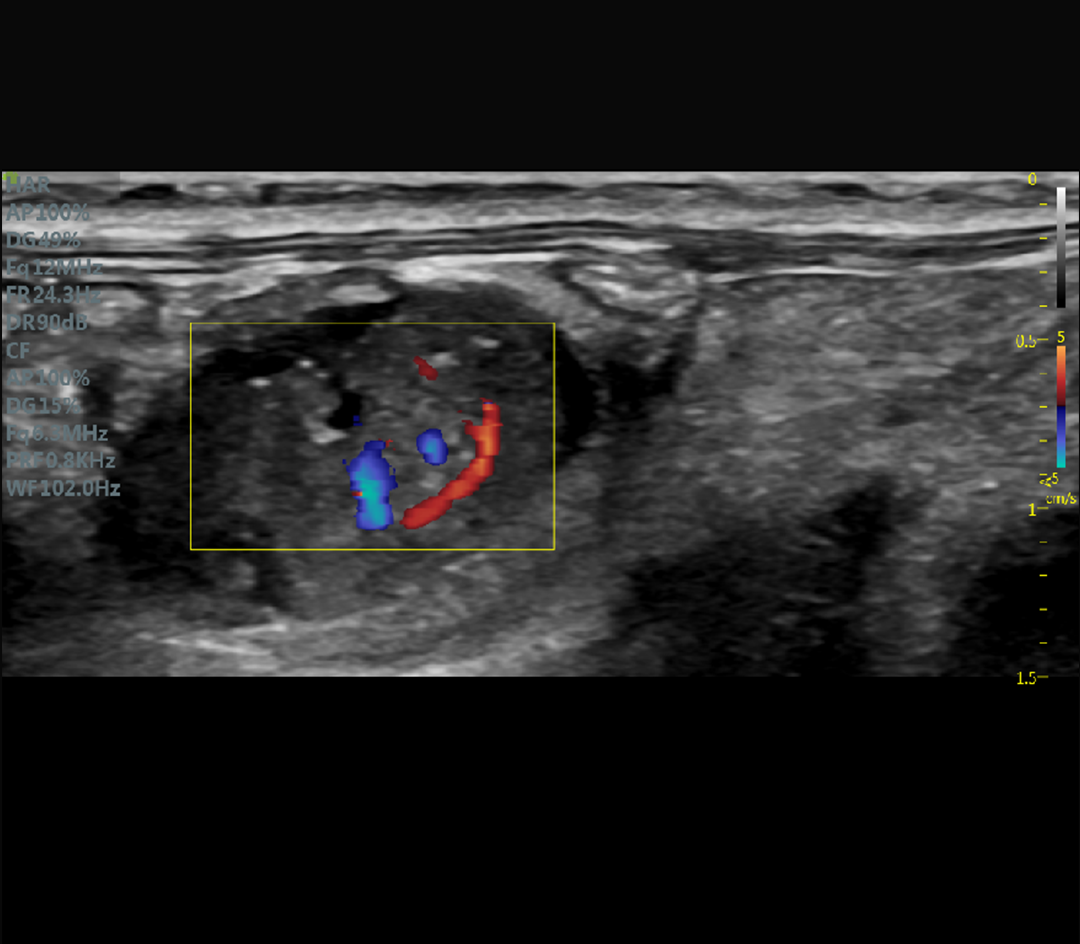

Le V6 LAB est un système d’échographie préclinique ultra-haute fréquence dédié à l’imagerie fonctionnelle et structurelle du petit animal.

Il combine traitement RF avancé, algorithmes d’imagerie Ultra HD et sondes haute fréquence pour fournir

des données fiables, reproductibles et exploitables en recherche.

Cardiovasculaire

Doppler couleur, pulsé et puissance

Doppler couleur, Doppler pulsé et Doppler puissance